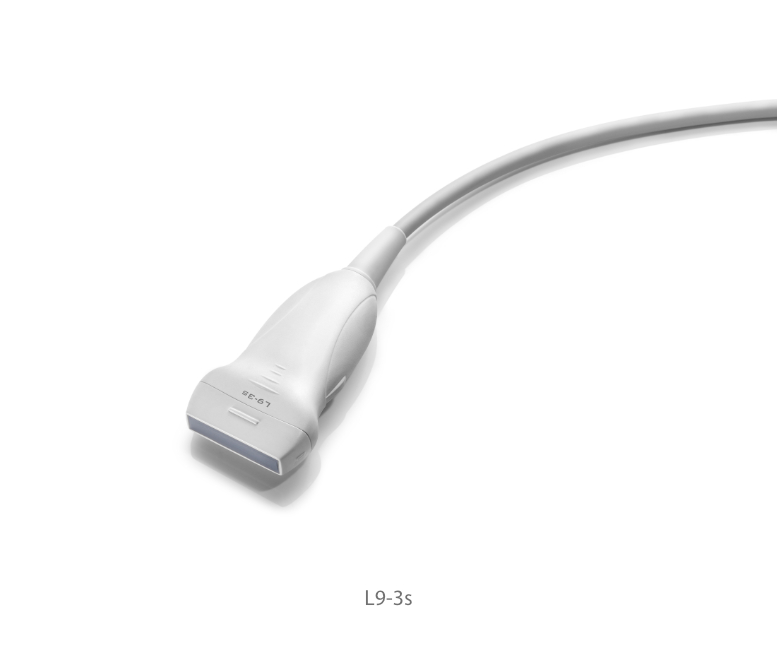

Transducers